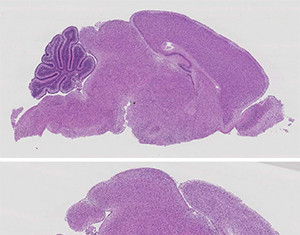

Bloquear el crecimiento del tumor cerebral con activación inmune

Investigadores de la Universidad del Instituto Cerebral Hotchkiss de Calgary (HBI) han hecho un descubrimiento que podría conducir a un mejor tratamiento para los...